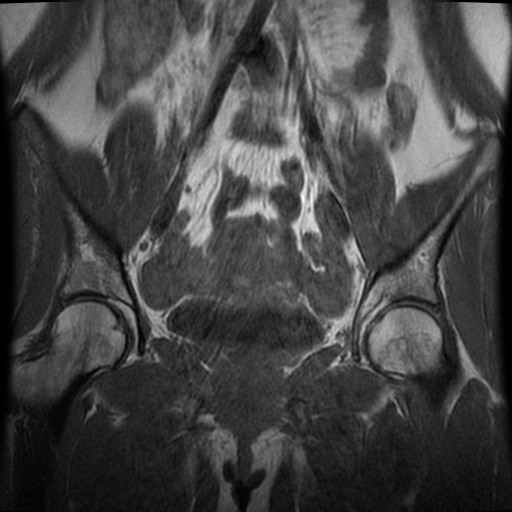

bekken